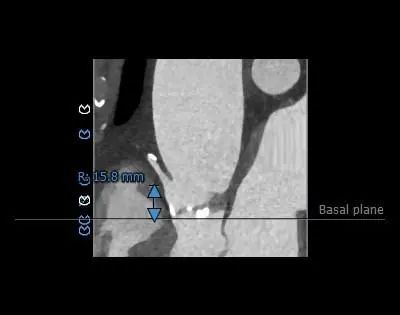

主动脉根部评估

CT 数据显示该患者为Type1型二叶式主动脉瓣

主动脉瓣瓣环周长72.5mm,周长径23.1mm

LVOT 周长 85.1mm,周长径27.1mm

SOV:31.1mm*33.6mm*31.6mm

STJ 周长 91.9mm

无冠瓣钙化严重,HU850:448mm³

瓣环水平夹角46度